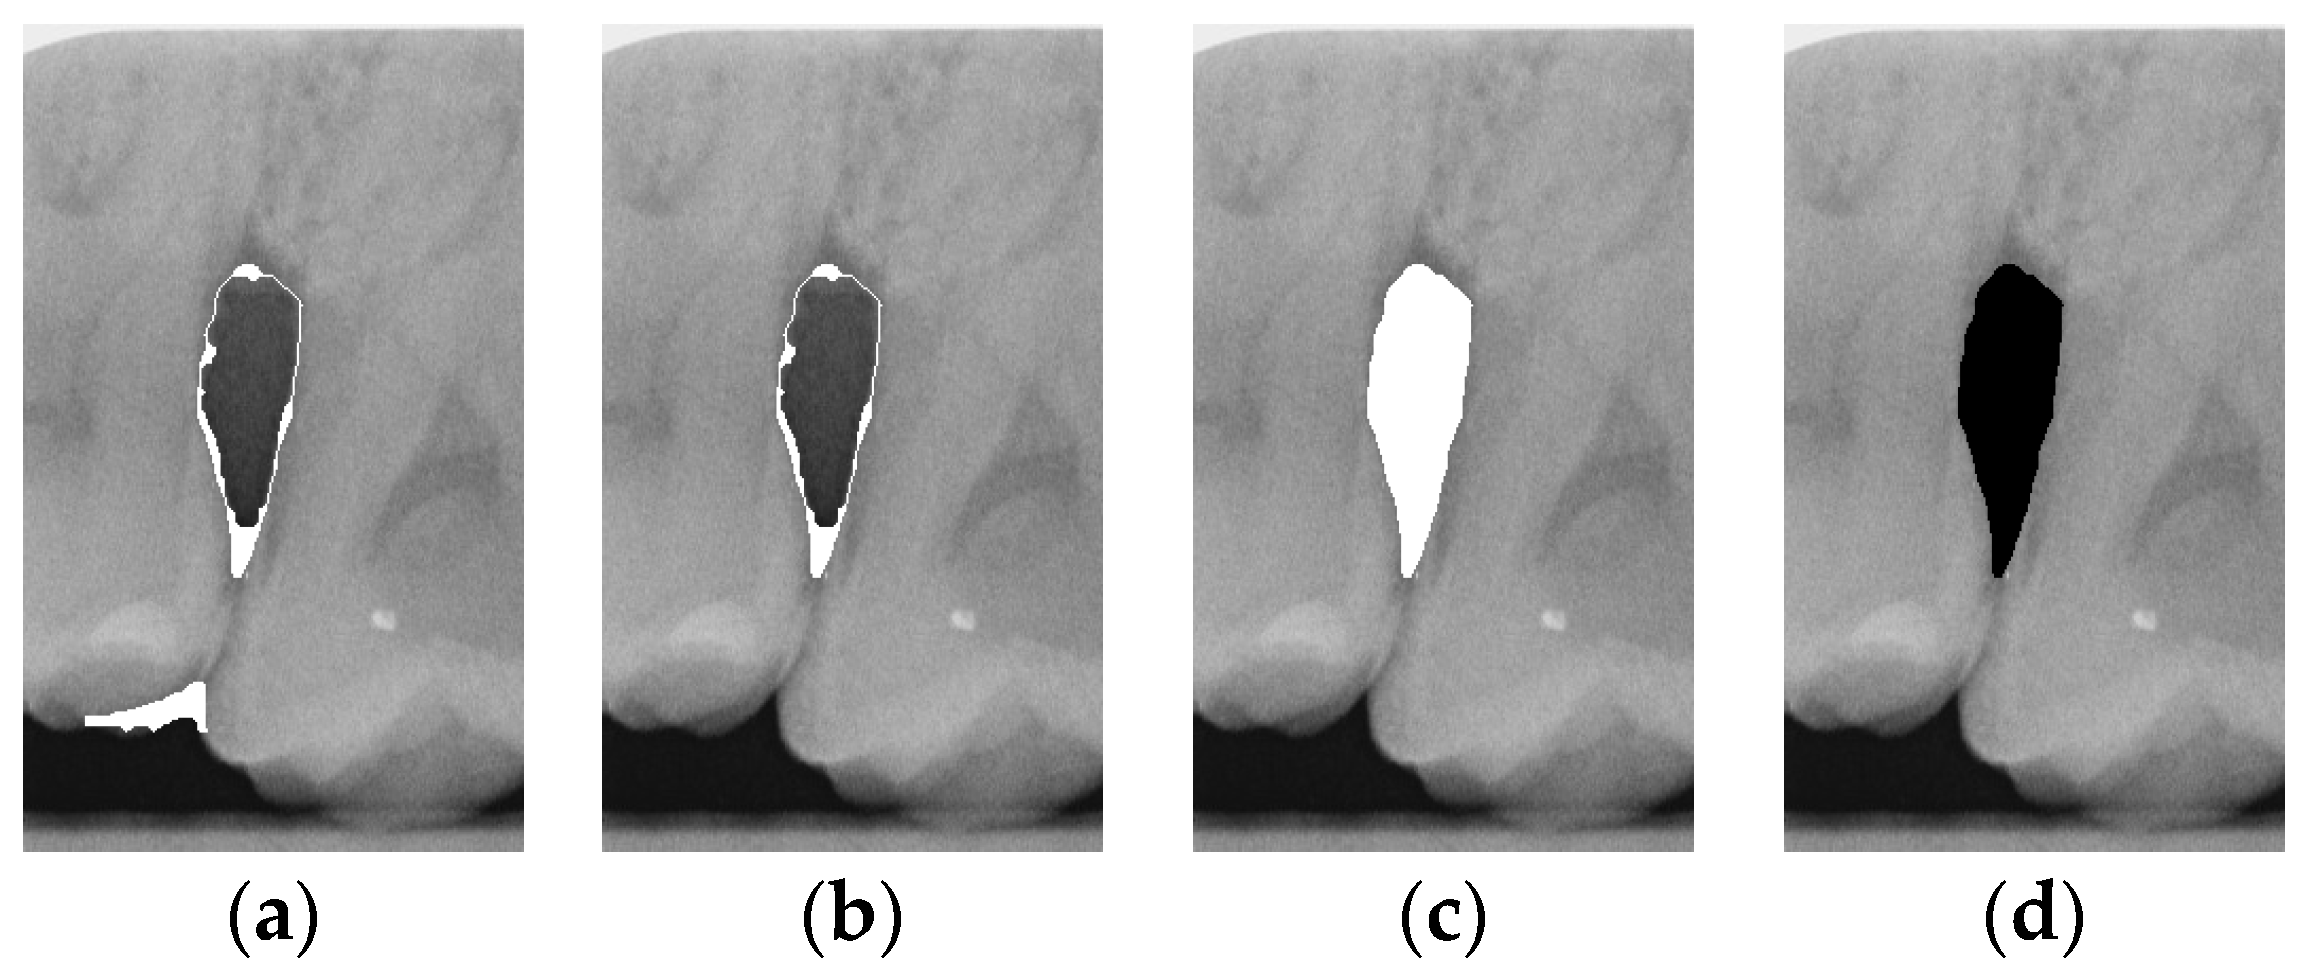

To ensure that only the area framing the symptom is preserved, and to remove the rest of the interfering areas or lines, the symptom frames are extracted according to the closure algorithm, i.e., the maximum connectivity area can be preserved to remove the frames of the non-symptomatic areas, as shown in Figure 7b. After the closure process, some of the frame lines are less smooth than others, which may affect the discrimination accuracy. To deal with this situation, this study performs the filling of the frame lines at the symptom area to facilitate the training of the model. Black and white are chosen to highlight the contrast and to compare the difference in discrimination between the two fill colors, as shown in Figure 7c,d.

Figure 7. Comparison of extracting the closed area and filling. (a) Close operation. (b) Extracting the closed area. (c) Filling with white. (d) Filling with black.